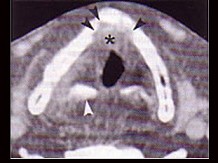

4.下面是一頸部CT圖,其中結構標志不正確的是  (    )

正確答案:D

6.CT檢查見下圖,進一步的檢查是  (    )